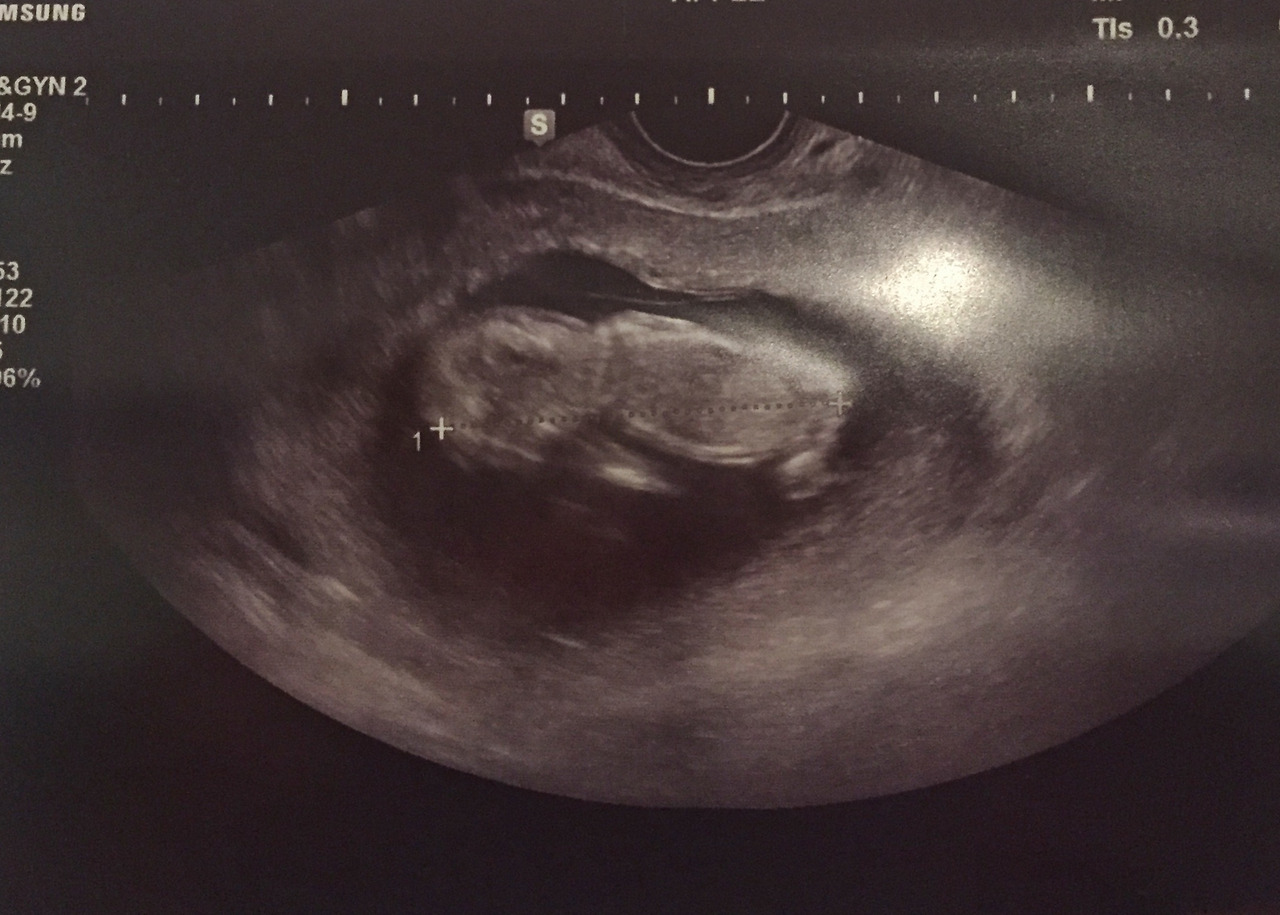

꼬물꼬물 아직 태아인 선물이

그리고 9월 27일, 25일 만에 선물이가 태어났다. 이날 새벽부터 아내는 출산통을 겪었는데, 예정일까지는 18일이나 남아있었다. 이른 아침 '설마 오늘 출산하겠어?'라는 생각으로 병원으로 향했는데 설마 오늘 출산했었다. 아내는 침착하게 소리 한번 지르지 않고 선물이를 낳았다. 용감한 아내의 모습이 멋지고 짠했다. 갓 태어난 선물이는 예상보다 작고 여렸다. 선물이를 처음 품에 안을 때는 너무 작고 소중해서 잘못 건드리면 큰일 날 것만 같은 느낌이 들었다. 그날 새벽부터 출산까지 12시간은 아직도 꿈만 같다. 평생 잊지 못할 것 같은 시간이었다. 이제 90일이 되가는 선물이는 오늘도 찡찡대면서 씩씩하게 크고 있다.